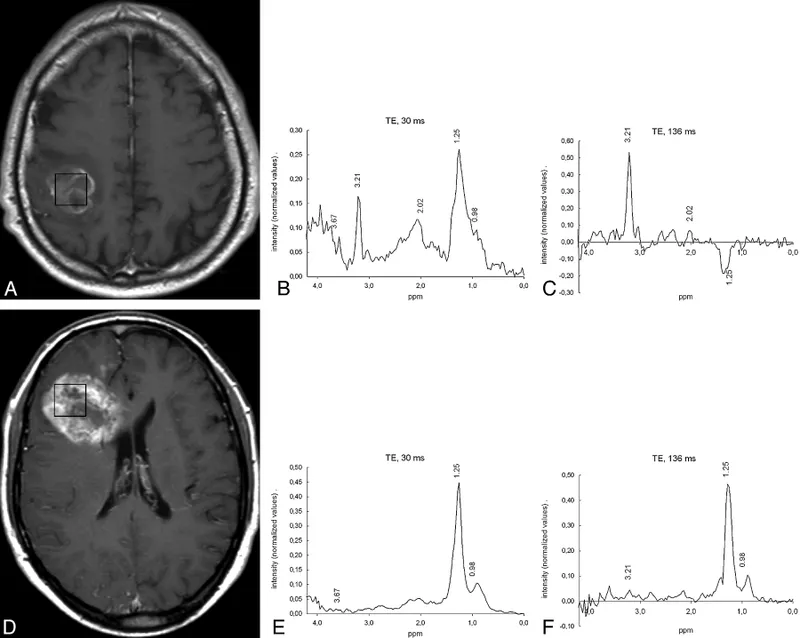

- Short TE (e.g., 20-35 ms): More metabolites (NAA, Cho, Cr, mI, Glx, Lip, Lac), complex baseline.

- Long TE (e.g., 135-144 ms, 270-288 ms): Fewer metabolites (NAA, Cho, Cr, Lac). Lactate doublet inverts at TE 144/272 ms (key for Lac detection).

- Brain Tumors: ↑ Cho, ↓ NAA, ↑ $Cho/NAA$ ratio, ↑ $Cho/Cr$ ratio. High-grade: Lac/Lip.

- Recurrence: ↑ Cho.

- Radiation Necrosis: ↓ Cho, ↓ NAA, ↓ Cr, prominent Lac/Lip.